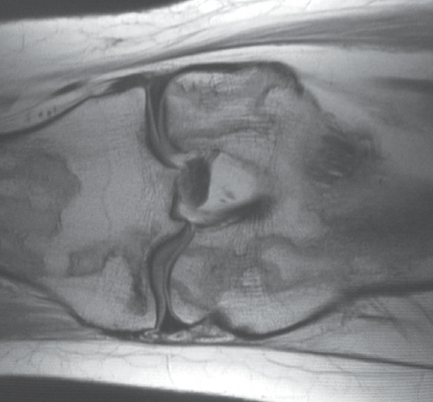

Due to the long-standing nature of the pain MRI of the knee was ordered. T1 and T2 (Figures 3-6) weighted images demonstrate serpiginous areas of increased and decreased signal paralleling each other consistent with the double line sign, which is classic for medullary infarcts of bone.

Figure 5. T1 weighted image in the whole plane coronal plane.

Figure 6. T1 weighted image in the sagittal plane.